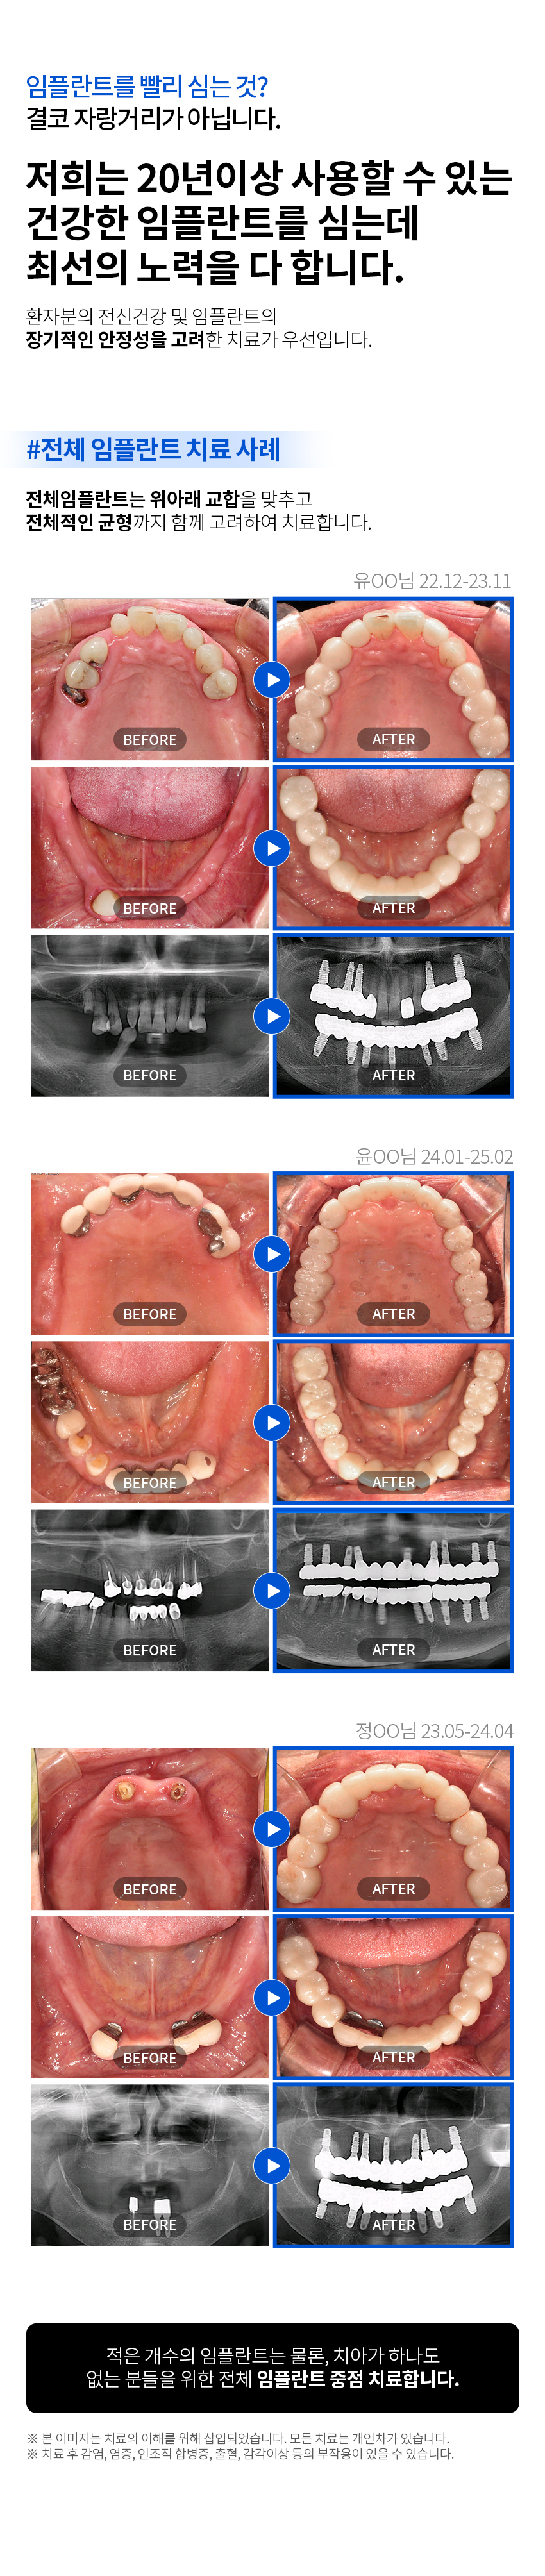

임플란트 임플란트종류 자가치아뼈이식 당일즉시 임플란트 맞춤 임플란트 재수술 임플란트 상악동 거상술 임플란트 보험안내